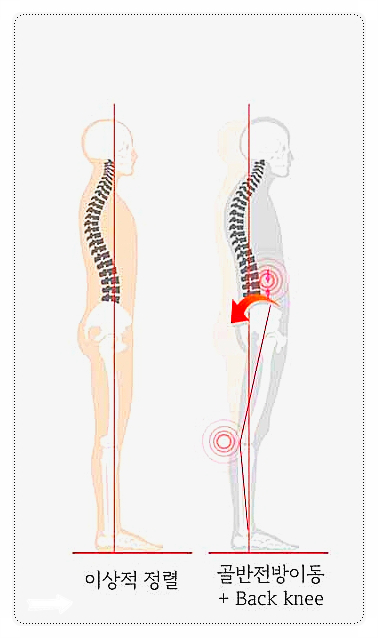

A. 삐딱한 골반이 허리 디스크를 괴롭히고 있어요.

우리 몸은 하나의 유기적인 사슬과 같습니다.

만약 골반이 틀어져 있다면 그 위에 얹혀 있는 척추는 중심을 잡기 위해 억지로 휘어지거나 특정 방향으로 힘을 더 쓰게 됩니다.

이 과정에서 요추 3, 4, 5번 디스크는 원래 견뎌야 할 무게보다 훨씬 무거운 압력을 받게 되죠.

기둥이 기우뚱하면 기둥만 만질게 아니라 바닥 지반(골반)부터 바로잡아야 하는 것과 같은 이치입니다.